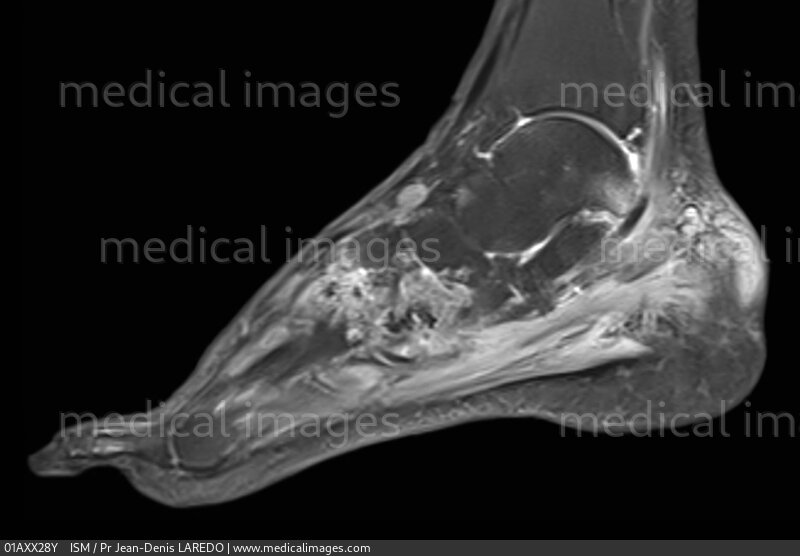

From www.medicalimages.com

STOCK IMAGE, mri of gout of the foot with tophaceous deposits tophi in Gouty Arthritis Foot Mri The purpose of this article is to review recent advances in imaging of gout and its clinical applications. The synovial fluid is a. Imaging is also essential when the. Acute gouty arthritis occurs due to the deposition of monosodium urate crystal (msu) within the synovial joint. The rheumatoid arthritis magnetic resonance image scoring system (ramris) is now commonly used to. Gouty Arthritis Foot Mri.